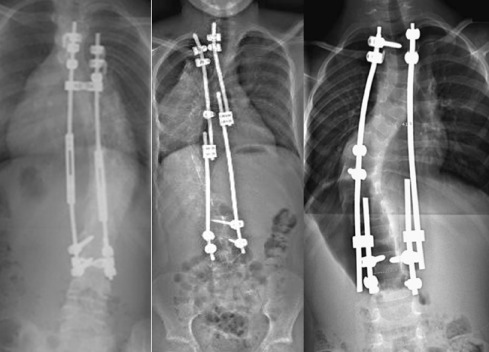

Quando una scoliosi supera i 50˚ Cobb, si definisce scoliosi grave.

E’ quasi certo che questa tipologia di scoliosi subirà una progressione della curva in età adulta e determinerà problemi di salute e una riduzione della qualità di vita. Infatti, i 45-50˚ Cobb sono la soglia generalmente riconosciuta per l’intervento chirurgico.

Solitamente le scoliosi più gravi sono quelle comparse in età infantile, o addirittura in età neonatale, poiché hanno maggior tempo a disposizione per peggiorare prima che la maturità scheletrica sia completata.